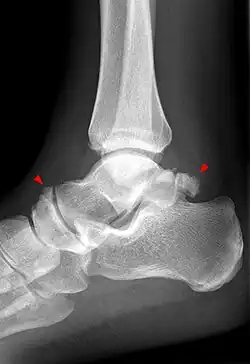

Das Os talonaviculare dorsale ist meist dreieckig und liegt im Gelenkraum zwischen Sprungbein und Kahnbein an der Oberkante am Fußrücken. Es gehört zu den häufigeren zusätzlichen Knochen (Prävalenz 1,6 %).[1] Das Knöchelchen kann entweder separat oder mit Verbindung zu benachbarten Knochen auftreten. Abzugrenzen ist es von Frakturen und Knochenabsprengungen von Talus oder Os naviculare oder von Rissen der Bänder des Gelenks zwischen Sprung- und Kahnbein, die mit Frakturen einhergehen (Abrissfraktur). Unterstützend bei der Diagnose ist die Tatsache, dass das Os talonaviculare dorsale meist (aber durchaus nicht immer![2]) beidseitig auftritt. So wird in einer Arbeit 1956 von 24 entsprechenden Befunden bei 783 untersuchten Füßen berichtet, wobei der Befund dreimal doppelseitig war.[3] Bei den von Pirie in seinen Originalarbeiten berichteten 14 Fällen waren vier bilateral.[4]